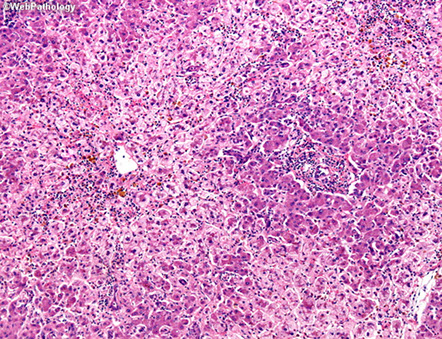

Hemophagocytic Syndrome

- caused by severe hyperinflammation c uncontrolled prolif of macrophages, clinically causing fever, cytopenia(s), and HSmegaly

- get inc ferritin, alk phos, triglycerides

- GLUT1 stain can highlight RBCs in macrophage cytoplasm

- sinusoids are at least mildly congested